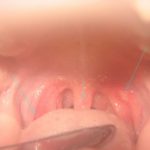

Stomatitis in infants

Stomatitis in infants (picture 7) can be detected with a thorough examination of the mucous membrane. The mucous membrane of the mouth is inflamed and has redness. The typical symptoms of thrush in infants: crying, moodiness, loss of appetite. Signs and symptoms depend on the form and degree of stomatitis in the baby. Stomatitis in infants brings anxiety to the child.

So, what does stomatitis look like in a baby:

- abundant salivation;

- swelling and redness of the mucous membrane;

- gums bleed.

Stomatitis in the baby passes with fever, fatigue, lethargy, headache, refusal to eat, whining child. In acute course of the disease, signs of stomatitis in children are very pronounced.